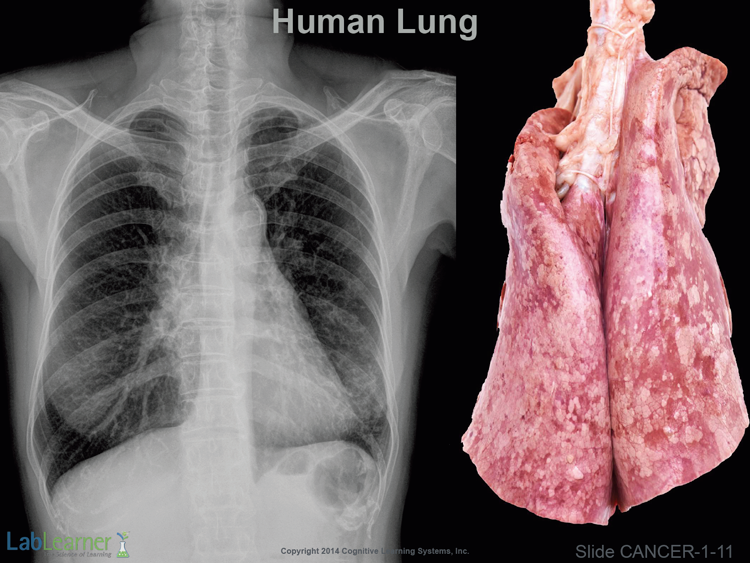

SLIDE CANCER-1-11

- This slide introduces lung tissue. In this introductory slide, we see a normal x-ray and gross specimen of the human lung. In anatomy and medicine, the term “gross” refers to macroscopic anatomy as opposed to embryonic anatomy, neuroanatomy, microscopic anatomy, etc. It does not mean gross as in disgusting, rank or crude as used in the common slang of “gross out”!

- Interestingly, one of America’s top nineteenth century surgeons and anatomists was a Dr. Samuel D. Gross who taught and practiced at Jefferson Medical College in Philadelphia and was immortalized by Thomas Eakins 1875 painting The Gross Clinic shown below:

- In Investigation 3, we will return to lung tissue and show x-ray and gross specimens of both healthy and cancerous lung.